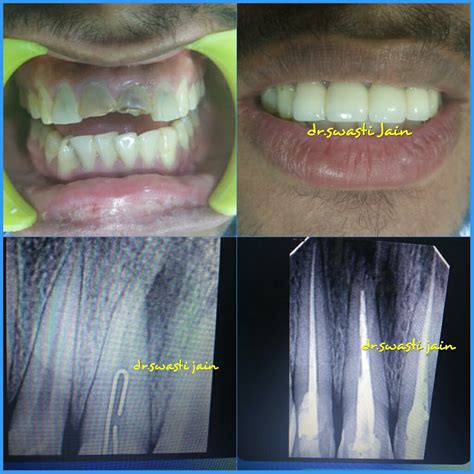

1. Diagnosis and Anesthesia: Your dentist will take X-rays to assess the extent of the infection. Local anesthesia is administered to ensure you do not feel pain during the treatment.

5. Restoration: Because a tooth that has undergone an Rct of teeth may become brittle, a crown or permanent filling is usually placed to protect it and restore its original functionality.

Following an Rct of teeth, your tooth may feel slightly sensitive, but this should subside within a few days. You can usually manage this with over-the-counter pain medication as recommended by your dentist. It is crucial to maintain excellent oral hygiene habits—brushing twice a day and flossing daily—to prevent reinfection. While a treated tooth can technically last a lifetime with proper care, regular check-ups are essential to ensure the seal remains intact and the surrounding bone remains healthy.